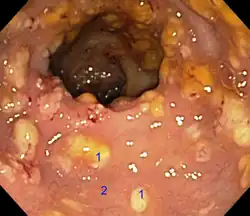

Рак образуется в форме опухоли, растущей в направлении отверстия толстой кишки, или в форме отёка, сужающего это отверстие. Большинство новообразований толстой кишки появляются в последнем её участке, что значительно облегчает лечение. Достижения в области диагностики и хирургии помогают выявлять и удалять раковые опухоли на ранних стадиях.

Тревожные симптомы, к которым относится прежде всего появление крови в кале, — основание для колоноскопии, то есть визуального исследования внутренности толстой кишки с помощью эндоскопа. Его трубка снабжена осветительным устройством и миниатюрной камерой, передающей изображение на большой цветной монитор. Применение эндоскопа позволяет осмотреть всю внутреннюю поверхность толстой кишки. В случае выявления мелких полипов их можно удалить, избежав злокачественного развития.